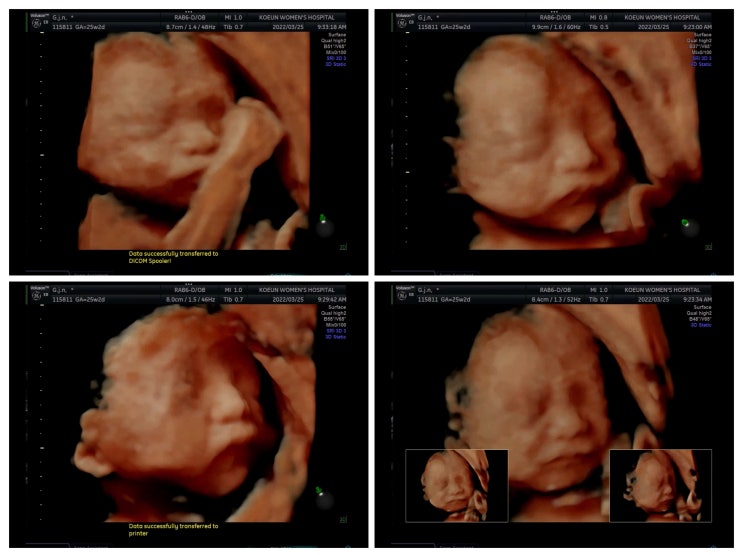

[임신 후기] 임신 7개월~8개월(25주~32주)_임당검사 / 3D 입체초음파 / 출산용품 준비

안녕하세요? 힐링타임 주인장이자 군산맘 지뮤입니다. 벌써 군산이가 찾아온지 8개월이 되어 드디어! 임...